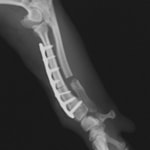

症例:柴犬 3歳

左後肢の完全挙上を主訴に来院されました。触診にて近位足根関節の過伸展を、レントゲン検査にて左足根関節周囲の軟部組織の腫脹、ストレス撮影によって距骨・踵骨と第4足根骨・中心足根骨間の脱臼および過伸展を認めました。

術中において、浅趾屈筋腱を剥離、内方へ牽引し、直接踵骨から第4足根骨までピンを挿入し(あらかじめ細いピンで下穴をあけておくとよい)、テンションバンドワイヤー法を併用し、関節軟骨の掻爬と海綿骨移植を実施しました。

術後レントゲン画像上に癒合が認められるまで約2ヵ月間は、運動を制限する必要があります。

術前側面像伸展位